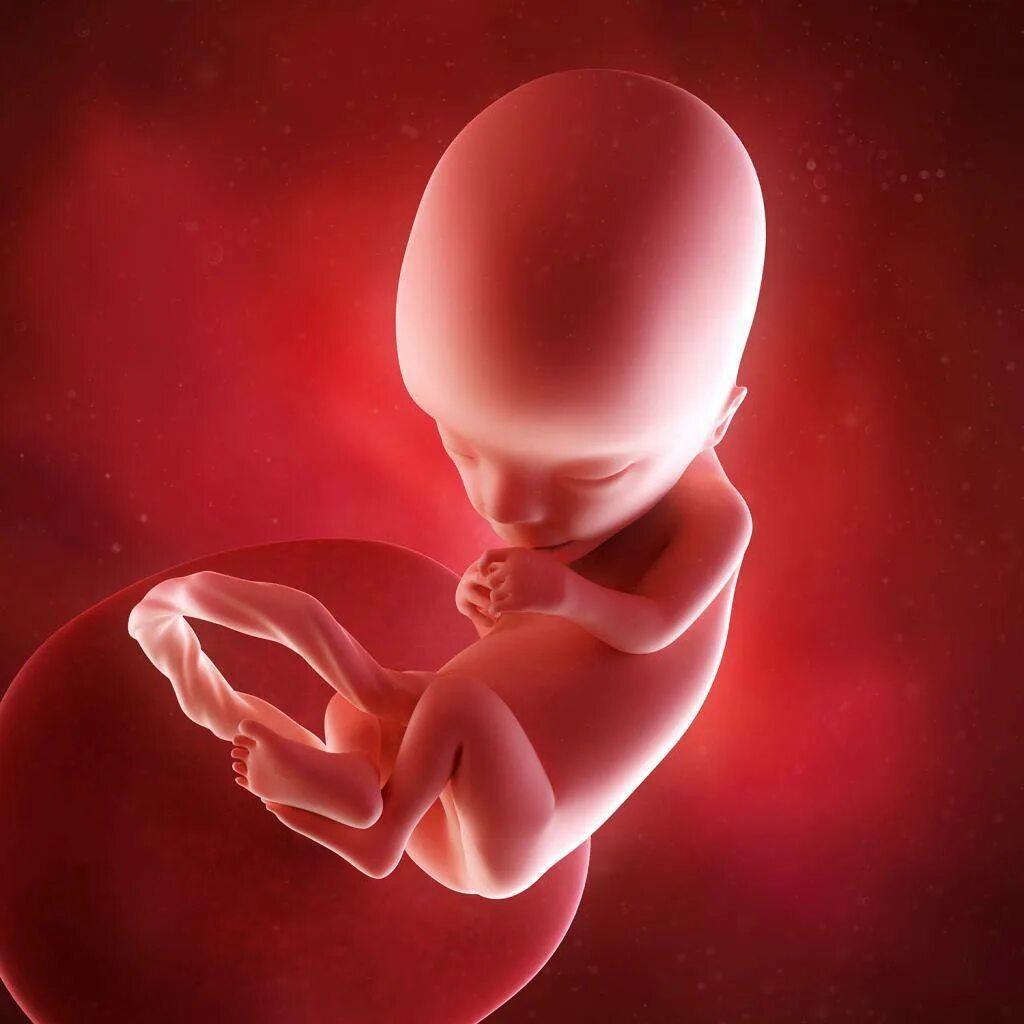

13 недель как выглядит малыш